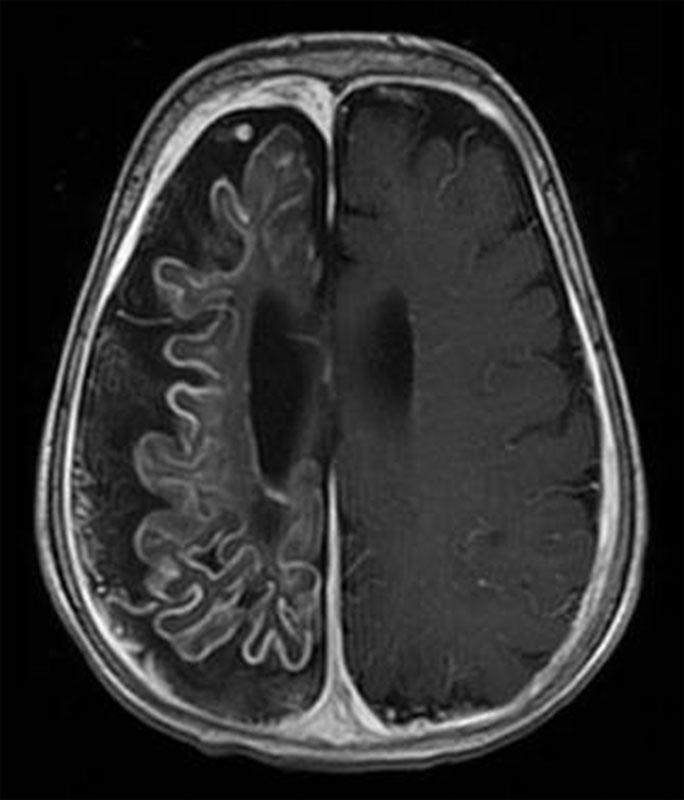

МРТ / КТ показано всем больным с парциальным началом / типом эпилептического припадка, а также при возникновении первого припадка после 30 лет без видимых причин. Обязательно осмотр офтальмолога (глазное дно), биохимические анализы крови, кардиологическое исследование и допплерография (особенно у лиц старшего и пожилого возраста), консультация психиатра (при сопутствующей патологии) и, по возможности, нейропсихолога.

К примеру, используемый в нашей клинике ультра-высокопольный магнитно-резонансный томограф позволяет получать высокоточные изображения головного мозга и находить даже самые маленькие очаги и аномалии развития, являющиеся причиной эпилепсии.

При поражении височной доли приступы, как правило, характеризуются нарушениями сознания в совокупности с ороалиментарными аурами (чувство «тошноты или чего-то поднимающегося изнутри вверх в горло или голову») и жестовыми автоматизмами (перебирание пальцами мелких предметов, краев одежды). Диагностика, как правило, при МРТ головного мозга выявляет признаки мезиального темпорального склероза.